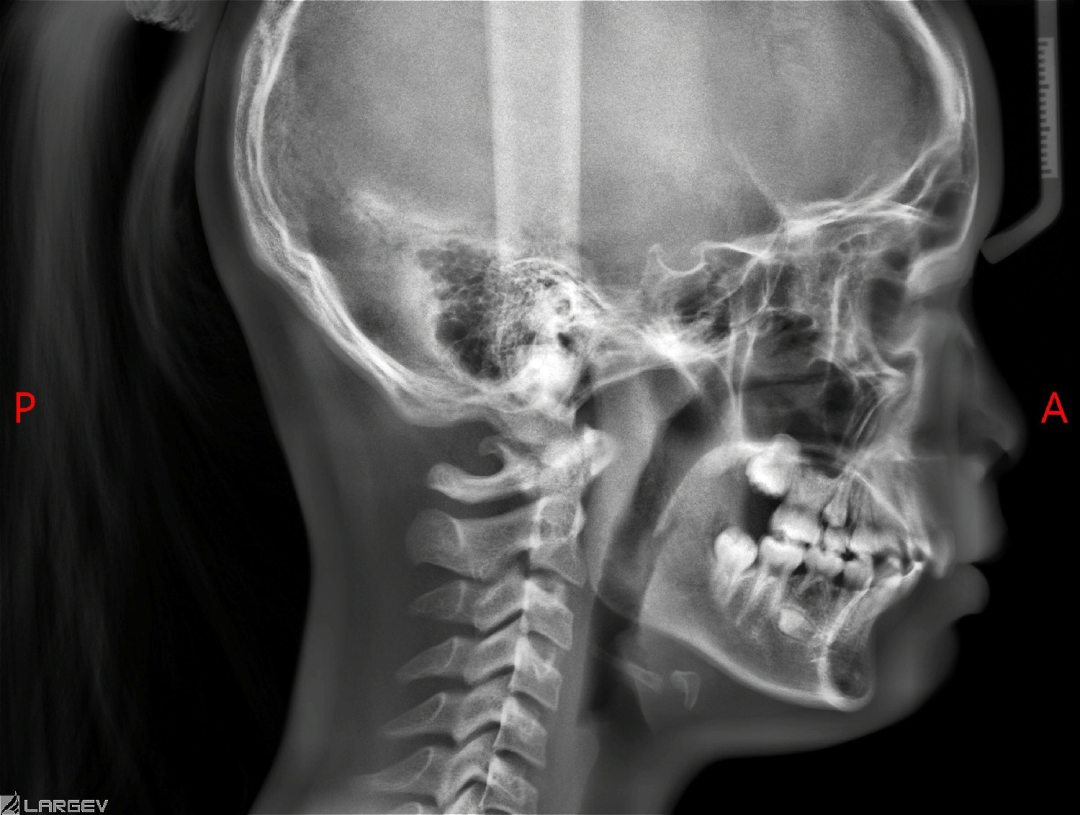

影响骨性下巴后缩矫治效果的主要因素是下颌骨垂直向发育的趋势,也就是高角、低角或者均角。

均角或者低角的骨性II类早期矫治效果通常会好。毕竟下颌骨的发育是正常的,随着生长的进行,下颌会逐步向前向上逆时针生长和改建,这是矫治骨性II类最需要的治疗方向。

而高角下巴后缩矫治效果相对均角或者低角下巴后缩,矫治效果需要的时间和下的功夫更多。

对于高角的II类下颌后缩问题,我们可以考虑使用Twin-Block功能矫治器,因为高角下巴后缩矫正策略是压低后牙,而Twin-Block功能矫治器恰好会带来后牙的压低。